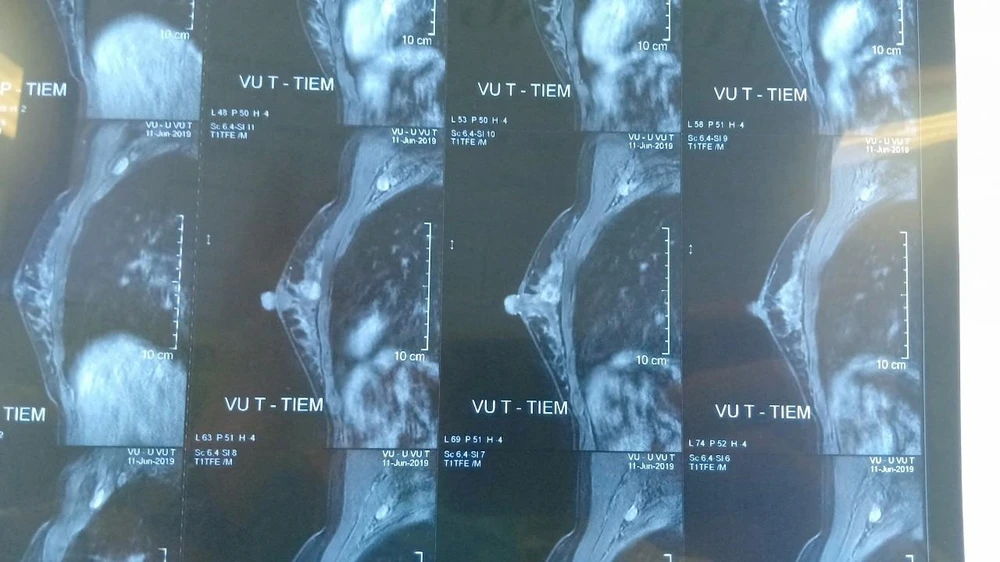

Hình ảnh phim chụp khối u của bệnh nhân T. trước khi phẫu thuật. Ảnh: M.T